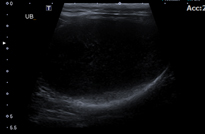

결석은 신장, 요관, 방광, 요도 등 비뇨기 중 어디에도 생성될 수 있습니다. 결석이 비뇨기 폐색을 유발할 경우 아이가 갑자기 뇨를 보지 못하고, 급성 신부전이 발생할 수 있어 응급 수술을 필요로 할 수 있으며, 아이에게 지속적인 불편감을 유발하여 혈뇨, 잔뇨감 등 다양한 임상증상을 나타낼 수 있습니다. 폐색이 유발된 부분, 증상, 재발 여부에 따라 SUB (인공요관우회술) 및 요도를 넓혀주는 수술 등이 필요할 수 있습니다. 본원에서는 내과 및 영상의학과와의 협진과 다수의 비뇨기계 수술 경력의 외과 수의사를 통해 아이에게 필요한 수술법으로 진행하고 있으며, 내과 전담 수의사를 통해 장기적으로 재발 관리 및 모니터링을 지속하고 있습니다.